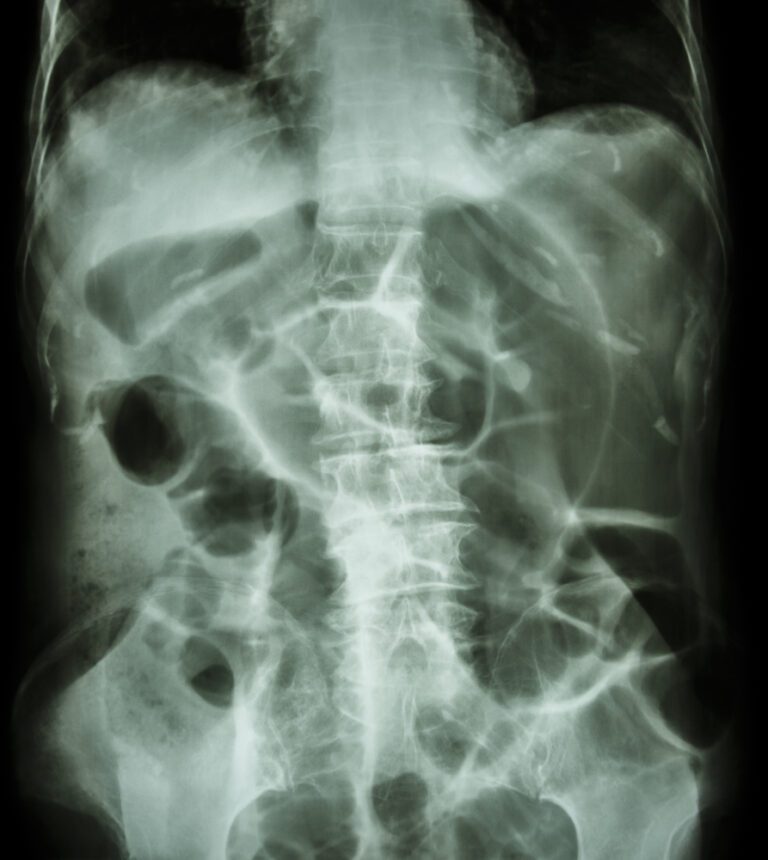

CT axial view peritoneal thickening and mechanical ileus. Download Mechanical Ileus Symptoms mechanical small bowel obstruction is caused by intraluminal or extraluminal mechanical compression. Most commonly presents 2 to 3 days. Ileus is a condition that occurs when the natural motion of the intestine that moves material along, called peristalsis, is slowed down or stopped. Feel bloated from a buildup of gas and liquid in your belly; ileus is a. Mechanical Ileus Symptoms.